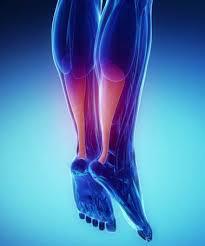

Εικόνα 1 : Απεικόνιση της τενοντοπάθειας του αχιλλείου. Διαθέσιμη στον διαδικτυακό ιστότοπο(https://www.google.gr/search?q=%CF%84%CE%B5%CE%BD%CE%BF%CE%BD%CF%84%CE%BF%CF%80%CE%B1%CE%B8%CE%B5%CE%B9%CE%B1+%CE%B1%CF%87%CE%B9%CE%BB%CE%BB%CE%B5%CE%B9%CE%BF%CF%85+%CF%84%CE%B5%CE%BD%CE%BF%CE%BD%CF%84%CE%B1&source=lnms&tbm=isch&sa=X&ved=0ahUKEwiS0LmbyfbeAhXFfFAKHUo6BpEQ_AUIDigB&biw=1252&bih=582#imgrc=_), (26/11/2018)

Η τενοντοπάθεια του αχιλλείου είναι ένας συχνός τραυματισμός υπέρχρησης που προκαλείται από επαναλαμβανόμενη αποθήκευση ενέργειας. Ο αχίλλειος τένοντας είναι ένας από τους πιο συχνά τραυματιζόμενους τένοντες στο ανθρώπινο σώμα παρά τη δύναμη του και μάλιστα όχι μόνο τραυματίζεται πιο συχνά αλλά είναι εκείνος που υπόκειται σε αυτό που ονομάζεται υπέρχρηση. Η υπέρχρηση είναι εξ ορισμού μια επαναλαμβανόμενη καταπόνηση που ενεργεί στον τένοντα, έτσι ώστε αυτός να μην μπορεί να αντέξει πια τάση και ένταση.

Οι ασθενείς (αθλητές και μη) με τενοντοπάθεια αχιλλείου συνήθως αναφέρουν πόνο στον τένοντα κατά τη διάρκεια της αρχικής φόρτωσης, επιδοκιμάζοντας τη συνεχιζόμενη δραστηριότητα. Καθώς η κατάσταση καθίσταται χρόνια, ο πόνος μπορεί να είναι επίμονος, με αποτέλεσμα την περικοπή της δραστηριότητας ή την παύση της. Η τενοντοπάθεια αχιλλείου ως κλινικό σύνδρομο χαρακτηρίζεται από τρία στοιχεία πόνο, οίδημα και λειτουργική βλάβη, που αντιστοιχούν στο ιστολογικό πρότυπο της τενόντωσης, όρος που δηλώνει μια μη φλεγμονώδη εκφυλιστική διαδικασία με μια δομή αποδιοργανωμένου κολλαγόνου.